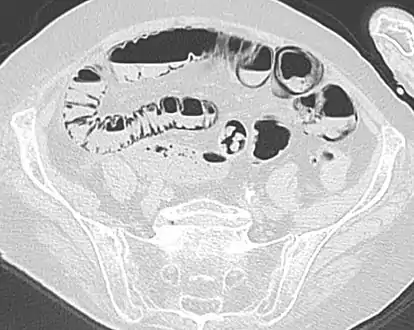

Pneumatosis intestinalis

Pneumatosis intestinalis (also called intestinal pneumatosis, pneumatosis cystoides intestinalis, pneumatosis coli, or intramural bowel gas) is pneumatosis of an intestine, that is, gas cysts in the bowel wall.[1][2] As a radiological sign it is highly suggestive for necrotizing enterocolitis. This is in contrast to gas in the intestinal lumen (which is relieved by flatulence). In newborns, pneumatosis intestinalis is considered diagnostic for necrotizing enterocolitis, and the gas is produced by bacteria in the bowel wall.[3] The pathogenesis of pneumatosis intestinalis is poorly understood and is likely multifactorial. PI itself is not a disease, but rather a clinical sign. In some cases, PI is an incidental finding, whereas in others, it portends a life-threatening intra-abdominal condition.